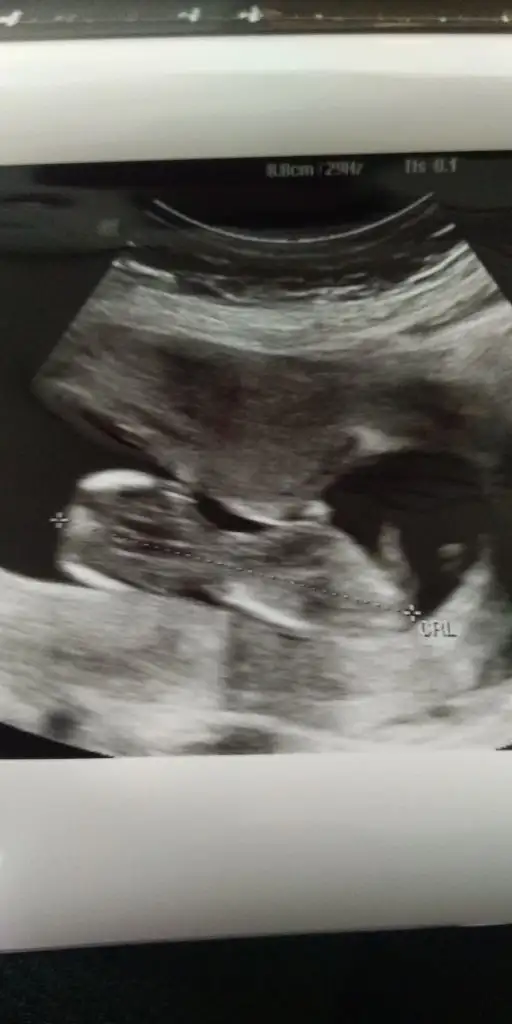

11 12 13 hafta olmalı cnmIkra meyra 15 haftalık bacakları kapalıydı. Erkeğe benzetti doktor. Sizdende bir tahmin alabilir miyim :)Eki Görüntüle 2655284

12+4 gunluguz.

cinsiyet tahmini alabilirmiyim.

doktorum koza benzetti ama emin olamadi:)

bide buraya sorayim dedim

hayirlisi insallah:)Net değil ama kız sanki paralel iniyor nubu kız gibi gibi